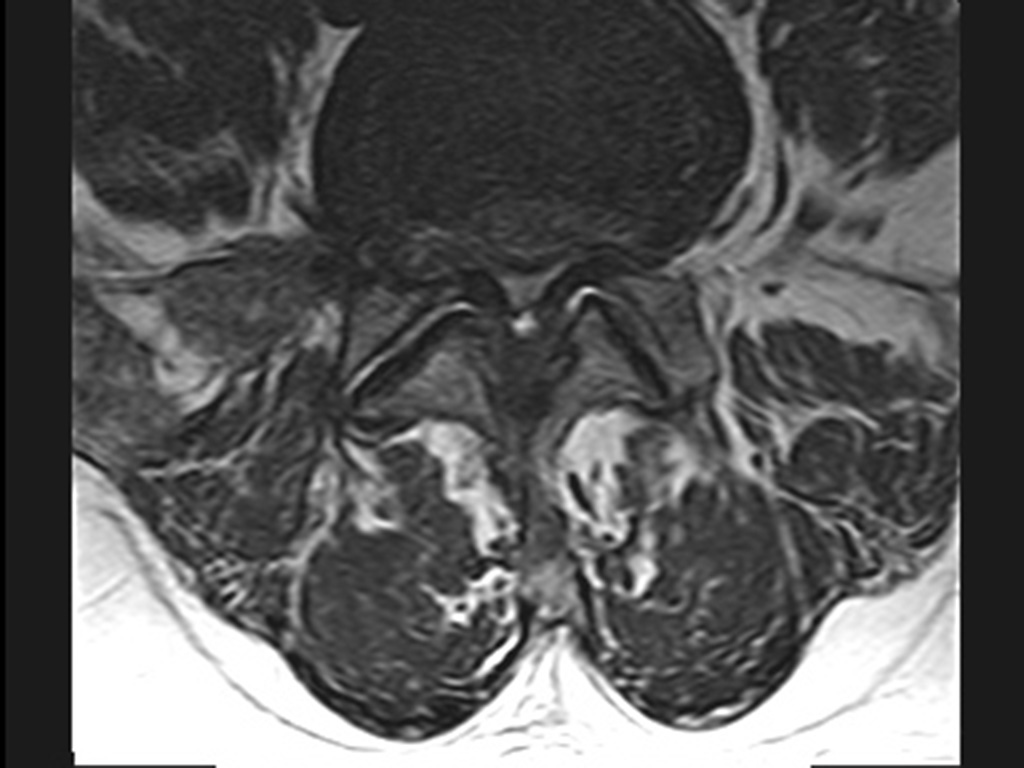

Stenosen des Wirbelkanals können durch Vergrößerung der Wirbelgelenke im Alter entstehen, aber auch durch Verdickung der Bänder zwischen den Wirbeln, durch Gelenkzysten oder durch übermäßige Vermehrung der Fettpolster im Wirbelkanal. All das kann dazu führen, dass der mit Nervenwasser (Liquor) gefüllte Nervenwurzelschlauch von außen so sehr komprimiert wird, dass es zu Schmerzen in den Beinen oder auch im Rücken unter Bewegung kommt. Die schmerzfreie Gehstrecke kann dabei auf wenige Meter schrumpfen, so dass die Mobilität erheblich eingeschränkt wird.